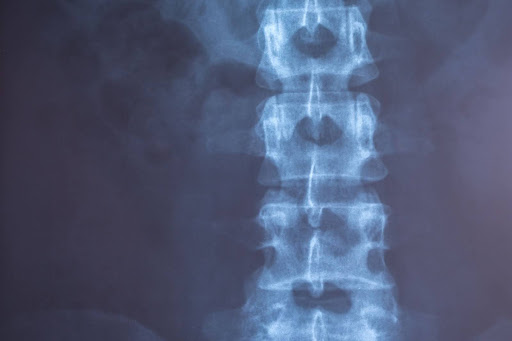

Выраженный болевой синдром при заболеваниях позвоночника и суставов часто сопровождается воспалением, мышечным спазмом и раздражением нервных структур. В подобных ситуациях традиционное медикаментозное лечение может давать лишь временный эффект. Для прицельного устранения причины боли применяются блокады под рентген-навигацией, позволяющие воздействовать непосредственно на патологический очаг с максимальной точностью и высоким уровнем безопасности.

Блокады под рентген-навигацией — это современный инвазивный метод терапии боли, основанный на введении лекарственных препаратов в строго определенную анатомическую зону. Процедура проводится под постоянным рентгенологическим контролем, что позволяет врачу визуализировать положение иглы относительно костных структур, суставов и нервных корешков. Это особенно важно при лечении глубоких и труднодоступных очагов, где ошибка в несколько миллиметров может снизить эффективность вмешательства.

При выполнении блокады под рентген-навигацией врач работает в условиях постоянной визуализации, контролируя направление и глубину введения иглы. Это принципиально отличает процедуру от инъекций, выполняемых без аппаратного контроля. Точное позиционирование позволяет доставить лекарственный состав непосредственно к зоне воспаления или компрессии нерва.